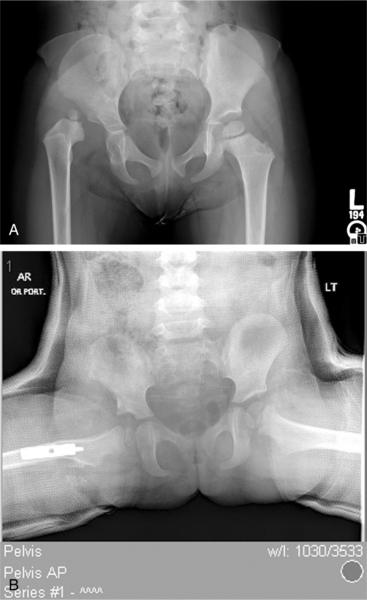

The subluxated hip maintains contact with the acetabulum but is not well seated within the hip joint. Often this occurs because the acetabulum is shallow, with the roof of the acetabulum sloping at an increased angle in people with DDH rather than showing a normal cup shape. The dislocated hip has no contact between the femoral head and the acetabulum, the femoral head sits on the iliac wing and the ligamentum teres is elongated and taut (Fig. 23-12).

Figure 23-12 Developmental dysplasia of the hip (DDH). Three-year-old child with unilateral developmentally dysplastic hip. A, Note the head of the femur sitting lateral to the acetabulum. The roof of the acetabulum appears dysplastic and the proximal femur somewhat valgus. B, Postoperative: the femur has been relocated in the acetabulum and a varus derotation osteotomy performed. A wedge is cut from the femoral shaft, then internally rotated and positioned in varus to correct the femoral anteversion and valgus. It is also common when there is acetabular insufficiency for portion of the iliac crest to be removed and used as a wedge above the acetabulum to deepen the acetabulum. (Courtesy Allan Glanzman, Children’s Seashore House of the Children’s Hospital of Philadelphia, PA.)